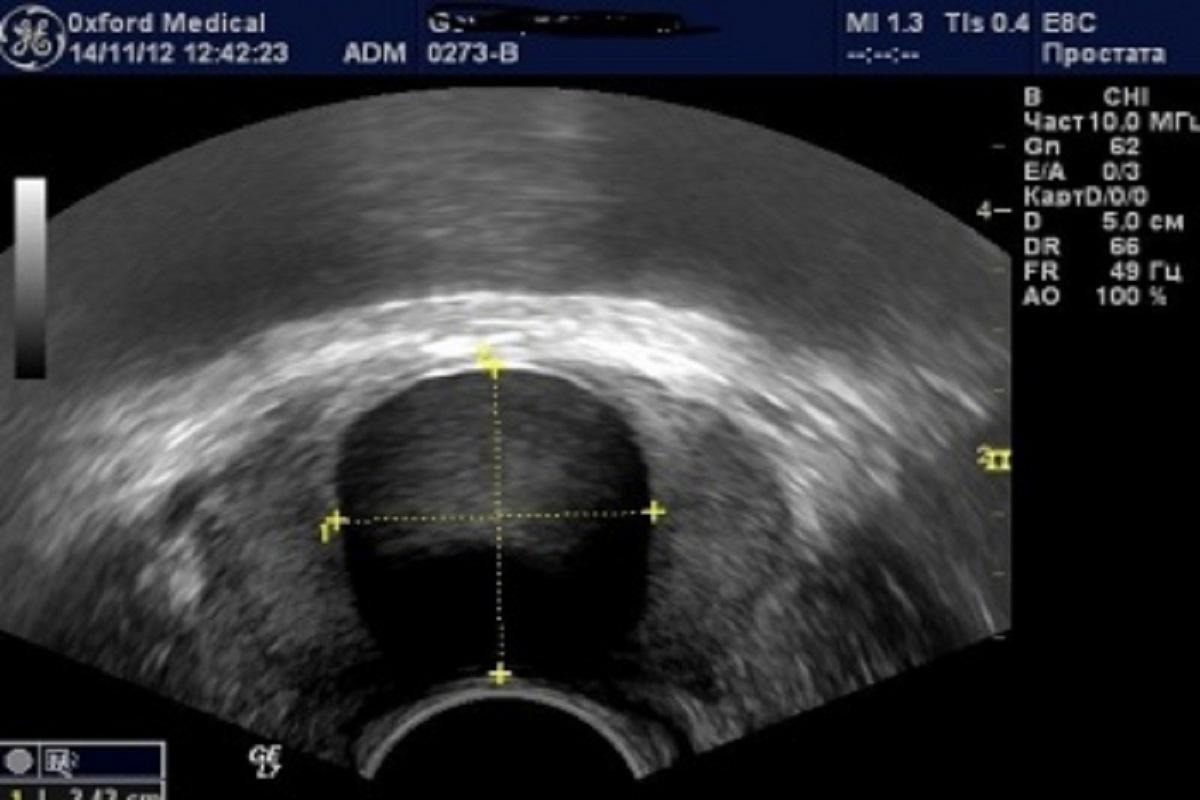

В Новосибирской области стали чаще выявлять рак простаты. В результате на сегодняшний день в структуре онкологических заболеваний данная патология занимает третье место.

При этом, отметили в Новосибирском областном онкодиспансере, у 73,5% больных болезнь выявлена на ранней стали. Всего на сегодняшний день рак простаты диагностирован у 1405 жителей региона.